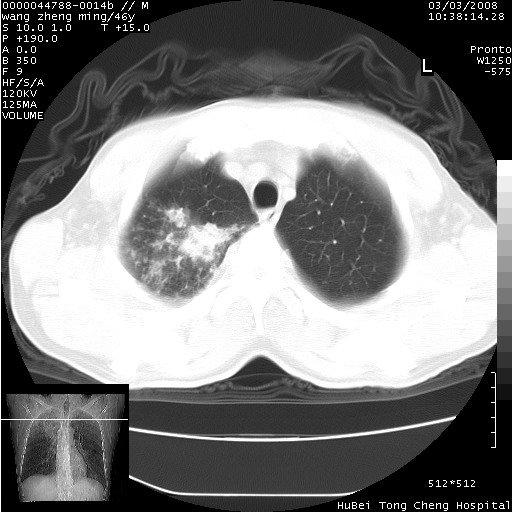

以下是引用卜一在2008-3-22 1:37:00的发言:[br]右肺实质性肿块,边缘不整,明显见毛刺征 分叶征及胸膜凹陷征,右上叶支气管明显变窄,远端散在的片状 斑片状实变影。另:左肺门较大肿块,支气管受累 变窄,远侧见阻塞性肺炎。纵隔内见肿大淋巴结。多考虑:右肺周围性肺癌伴左肺门 纵隔淋巴结转移!